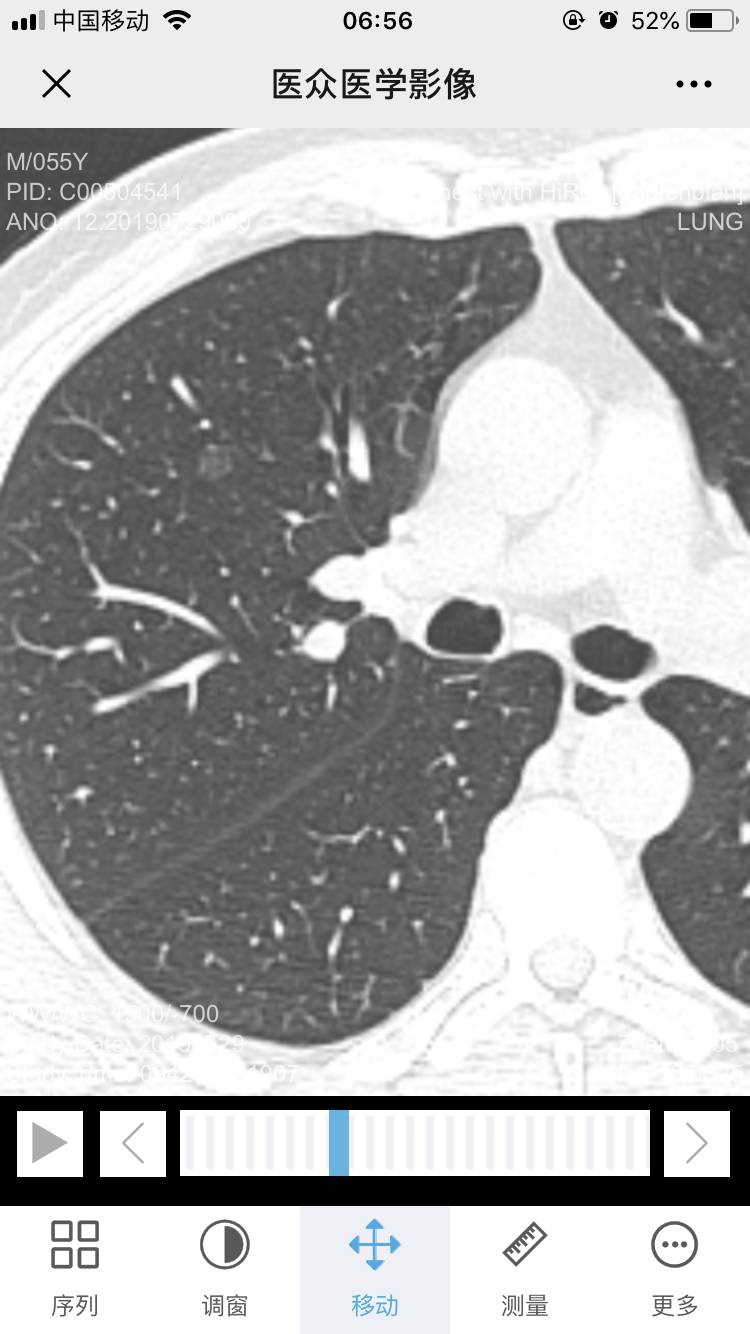

陈波医生如图